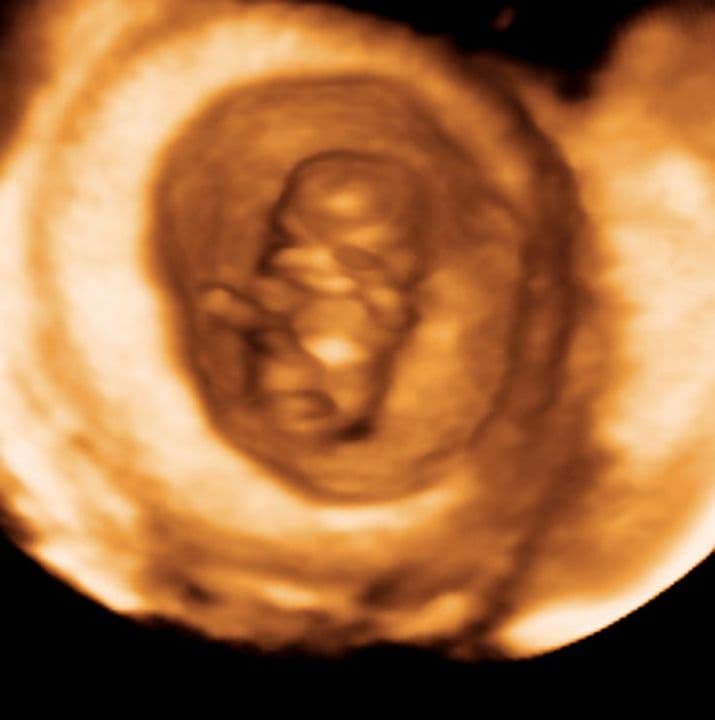

9 weeks and 3 days pregnant

The shoulders, elbows, and wrists are flexed leaving the hands in front of the face. It’s far too early to be aware of them but several fetal movements will start to become apparent on an ultrasound scan at this stage.